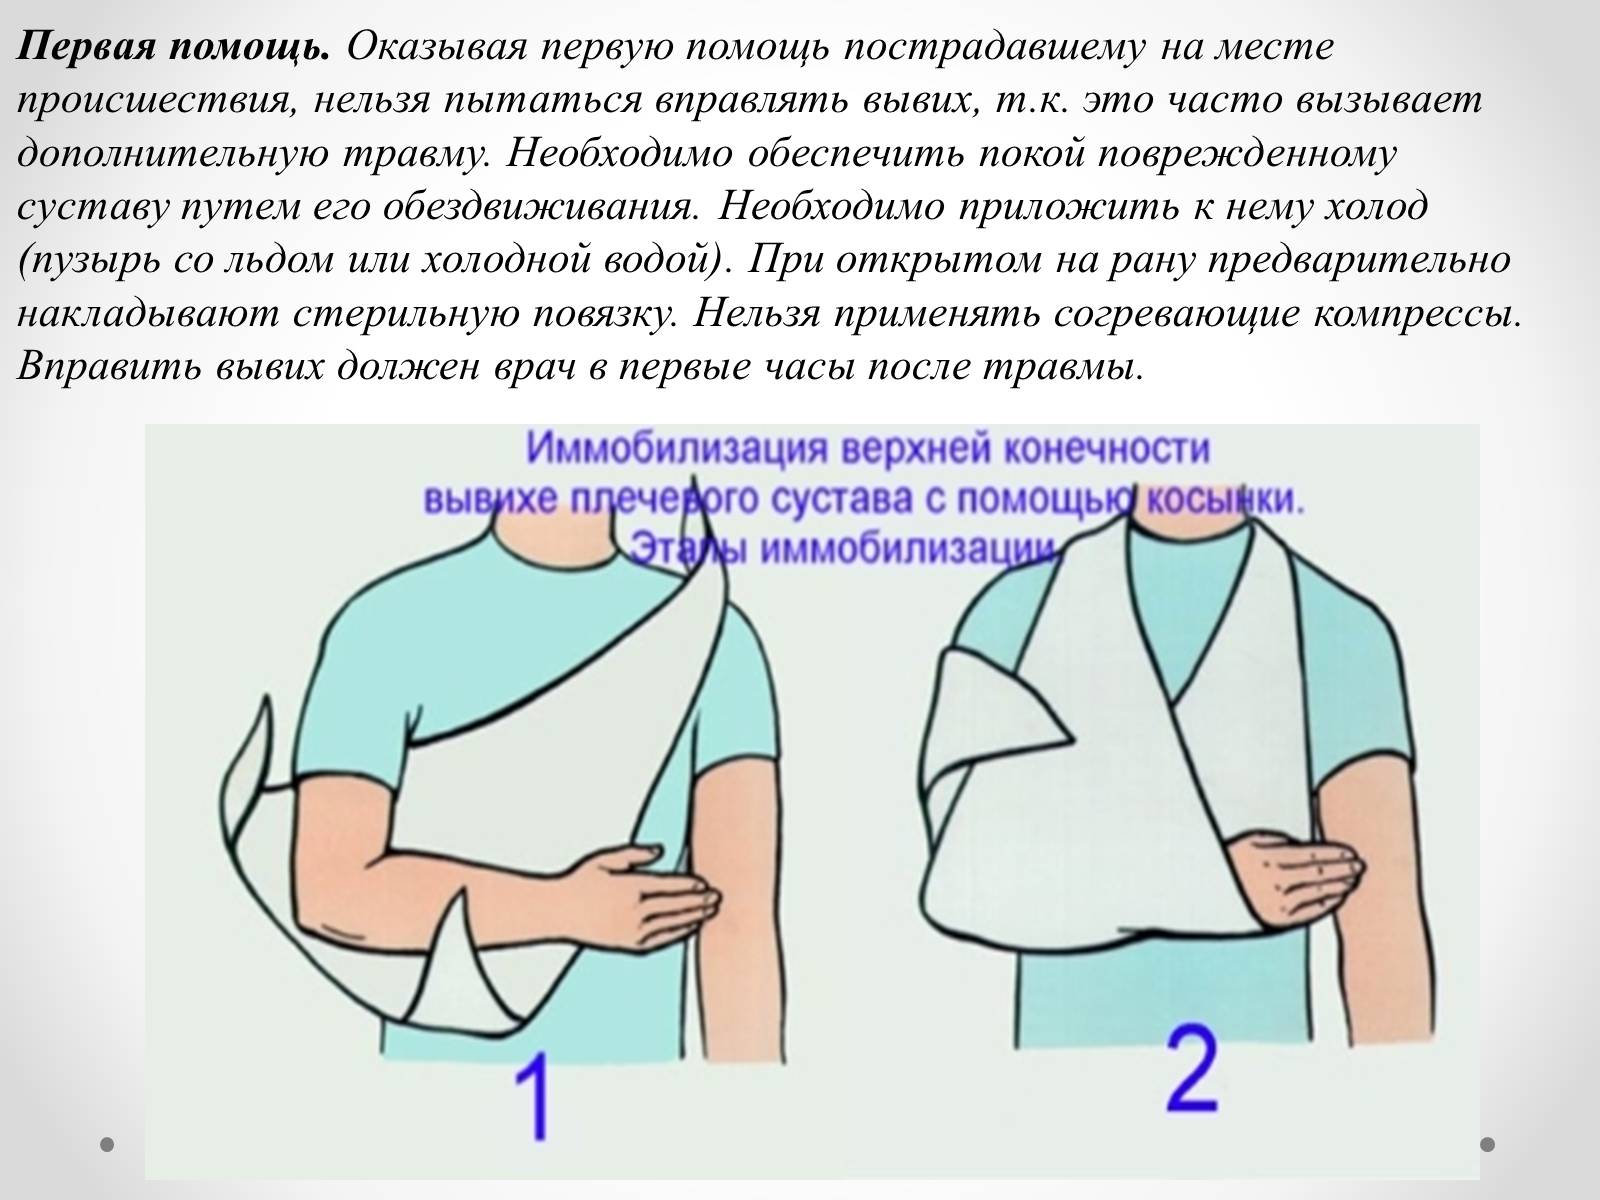

Вывихи и переломы ключицы презентация - 85 фото